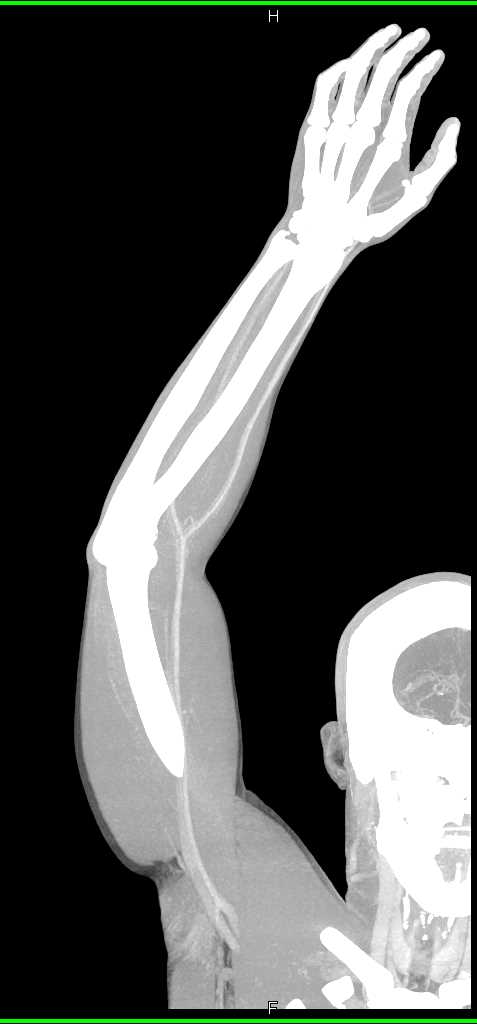

Soft Tissue Injury with Patent Vessels